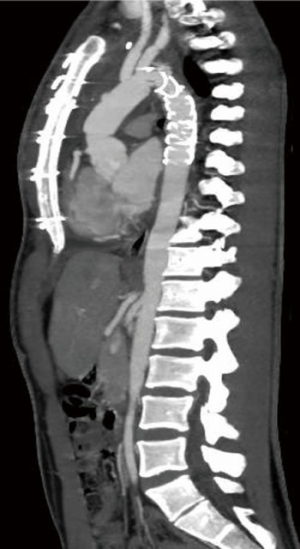

Two weeks after the operation the patient was discharged in good health. The postoperative period was uneventful and the CT angiogram at postoperative day 10 showed the complete exclusion of the pseudoaneurysm of the aortic isthmus (Figure 2B) and a normal morphology of the Thoraflex hybrid prosthesis and of the re-implanted supra-aortic trunks (Figure 3).